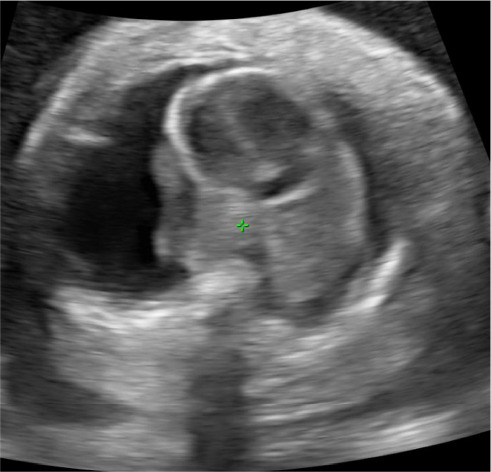

Nonimmune hydrops fetalis (NIHF) refers to the pathologic accumulation of fluid within the fetus due to causes other than red cell alloimmunization and now accounts for up to 90% of fetal hydrops cases. Fetal hydrops is associated with significant morbidity and mortality, and the exact prognosis is largely dependent on the underlying etiology. The most common etiologies include cardiovascular causes and chromosomal or genetic abnormalities. Despite this, diagnostic testing with karyotype or chromosomal microarray only identifies approximately 25% of cases, and up to 20% of cases remain idiopathic or unknown. We report the first known case of NIHF related to a NOTCH1 pathogenic variant. In this case, NIHF was diagnosed at 30 weeks' gestation in a fetus with low-risk prenatal genetic screening, noncontributory anatomic survey, and normal chromosomal microarray. The hydrops was uniquely localized to scalp edema and pleural effusions requiring bilateral thoracentesis and never progressed to involve pericardial effusion or ascites. Whole exome sequencing diagnosed a novel pathogenic variant in the NOTCH1 gene. This is the first reported case of NIHF in the setting of NOTCH1 pathogenic variant and is an important addition to the existing literature on this incredibly diverse, high-risk pathology.

Abstract Image